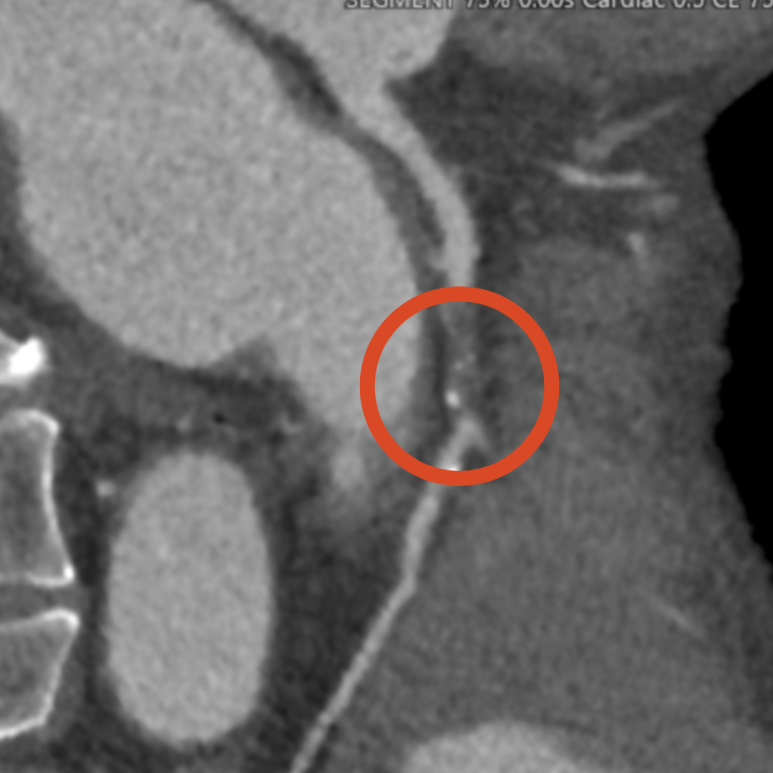

ECG·심초음파 특이 소견 없음. 관상동맥 CT 검사 결과 좌관상동맥 2부위 중증 협착 명확히 확인되었고, 즉시 스텐트 치료 필요성 높아 상급병원으로 전원.

• 3D 관상동맥: 협착 부위 3D 관상동맥: 협착 부위

• 좌측 관상동맥 2곳에서 협착 발견 좌측 관상동맥 2곳에서 협착 발견